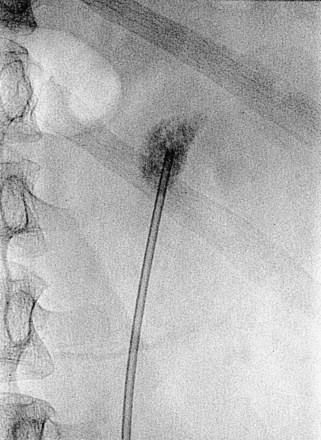

Balloon dilators (Fig. 47–25) were developed to obviate the repetitive dilations of the rigid metal and semirigid plastic dilation systems, which are both time consuming and potentially dangerous. This is the most common dilation method for percutaneous renal surgery today (Benway and Nakada, 2008). The appropriate working sheath is back-loaded onto the balloon dilation catheter, which is passed over the working wire until the radiopaque marker is at the intended depth of dilation (Fig. 47–26). The dilating balloon is inflated with a pressure syringe. A “waist” appears at the site(s) of greatest resistance, usually the abdominal wall fascia and the renal capsule (Fig. 47–26B). Once the balloon is fully expanded (Fig. 47–26C), the working sheath is passed over the balloon (Fig. 47–26D) (Fig. 47–27 on the Expert Consult website

). The balloon catheter has a “shoulder,” which is the portion between the end of the balloon and the point at which the maximal diameter is achieved. The sheath should not be passed beyond the maximal diameter of the balloon because this can cause significant injury. Balloon dilators, which are expensive one-time use devices, are less effective than rigid metal and semirigid plastic dilation systems in densely scarred tissue but are more effective when the kidney is hypermobile (Kumar and Keeley, 2008). Most (Heggagi et al, 1991; Davidoff and Bellman, 1997; Safak et al, 2003; Kukreja et al, 2004), but not all (Gonen et al, 2008a), studies have suggested that hemorrhage and transfusion rates are less with the balloon dilators compared with rigid metal and semirigid plastic dilators.

Figure 47–26 Balloon dilation of tract and placement of working sheath. A, Balloon catheter is inserted over wire, with distal radiopaque marker is at the intended depth of dilation. B, “Waist” appears as balloon is inflated. C, Balloon is fully expanded. D, Sheath is passed over balloon, taking care not to advance it beyond the point of maximal diameter of the balloon.